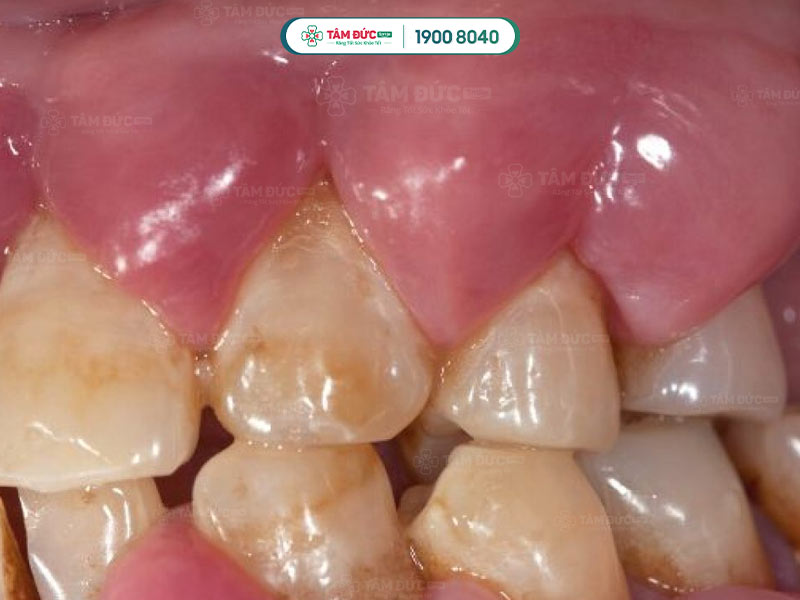

1.2.3. Áp xe nha chu

- Xảy ra khi vi khuẩn xâm nhập qua các lỗ nhỏ trên răng và nướu.

- Thường do các mảng bám tích tụ dọc theo đường viền nướu và cứng lại thành cao răng.

- Các cao răng này tích tụ gây kích ứng mô nướu, dẫn đến viêm và nhiễm trùng nướu. Khi viêm bắt đầu trở nên nghiêm trọng, mô nướu chết dần và xảy ra mất xương.

- Nhiễm trùng nha chu nặng làm nướu tách khỏi chân răng, làm răng lung lay và gãy rụng. Quý khách cần điều trị nhiễm trùng nha chu sớm để ngăn ngừa nhiễm trùng lan rộng gây mất răng.

Áp xe nha chu